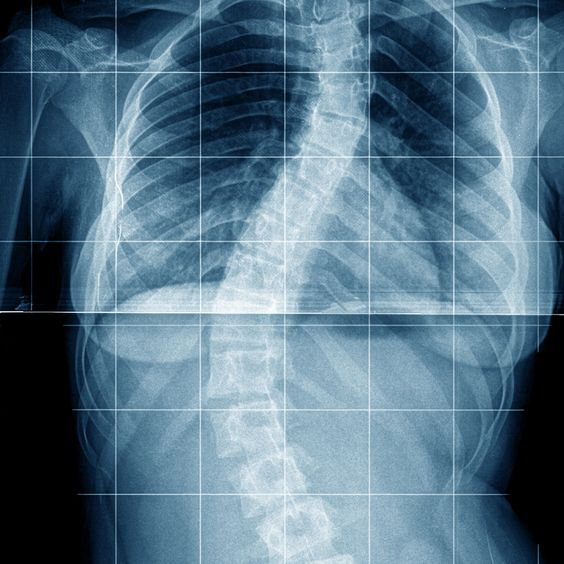

Ген сколиоза – миф. Как возникает искривление позвоночника на самом деле?

Несмотря на предрассудки, конкретная причина подросткового идиопатического сколиоза до сих пор не установлена. Исследования лишь признают генетические или наследственные факторы, которые совокупно влияют на появление болезни у ребенка. Нет одного гена, на который можно переложить ответственность за сколиоз и закрыть на все глаза, дескать, ничего нельзя сделать. К тому же, следует разделять генетику и наследственность. Это разные вещи. Пример: При исследовании семьи, в которой было выявлено 11 пораженных членов в трех поколениях, ученые И.Чан и Олден находили участки хромосом, связанные со сколиозом. Но прямое доказательство, что мутация хотя бы одного гена вызывает семейный сколиоз, или влияет на степень бокового искривления, так и не было представлено. Помимо генетики есть питание, благодаря которому организм получает строительный материал, привычки семьи заниматься спортом или вести сидячий образ жизни, который копируют дети. Генетика может создать предпосылку, при которой болезнь бу